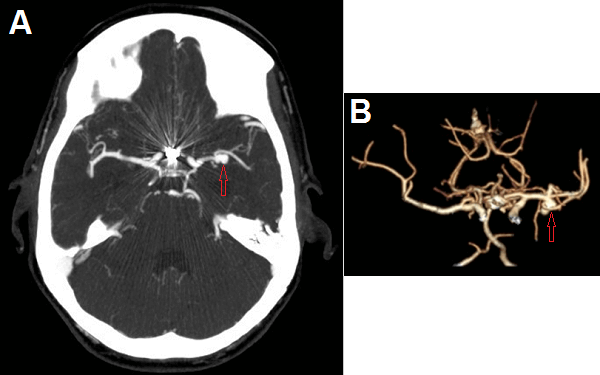

History : 45 year old man with sudden onset of severe headache.

What is the most likely etiology for this patient’s intraventricular hemorrhage?

Answer: MCA Aneursym. The images demonstrate an intensely vascular mass in the right supraclinoid region. The mass appears to communicate with the adjacent vasculature and is most consistent with an aneurysm.

(A) axial CTA head demonstrates a distal left middle cerebral artery (MCA) aneurysm

(B) shaded surface display (SSD) reconstruction demonstrates the 3 dimensions of the M1 segment aneurysm which incorporates the origin of the inferior division of the M2 segment (blue arrow)

Ruptured aneurysms typically produce subarachnoid hemorrhage associated with a classic clinical presentation – the thunderclap headache or worst headache of a patient’s life. However, depending on their location, aneurysms can also selectively dissect into the brain parenchyma (proceeding intracranial hemorrhage) or into the ventricles (intraventricular hemorrhage) as in this case.